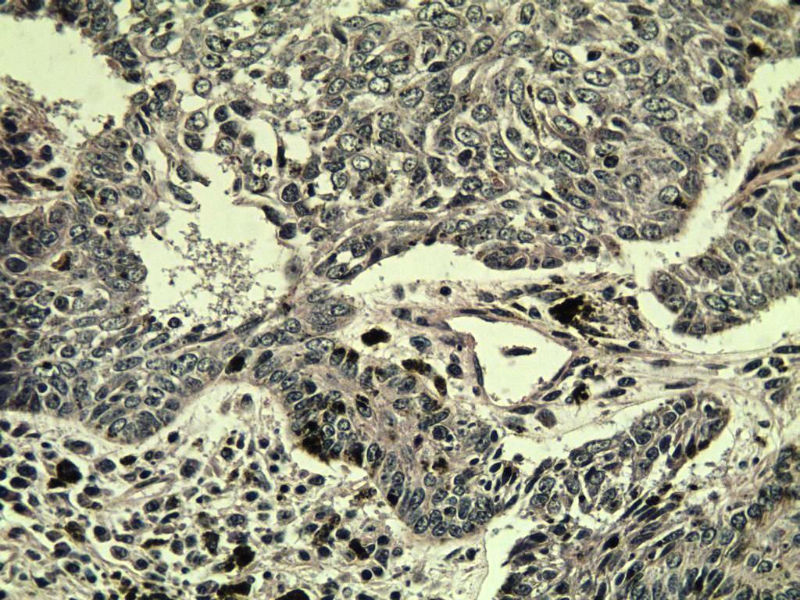

这是另外一个  75岁 男性 脸上有一直径0.8cm新生物 是鳞癌吗? 感觉细胞异型性不够大.

第二例:基底细胞癌

第二例,两种成分,1、毛发上皮瘤;2、皮内痣。

第一例考虑毛母细胞瘤,第二例考虑基底细胞癌。

第一例:毛母细胞瘤;第二例:基底细胞癌

第一例,毛发上皮瘤;第二例,基底细胞癌。

1.BCC.  2.BCC.

二基底细胞癌。

两例均为BCC